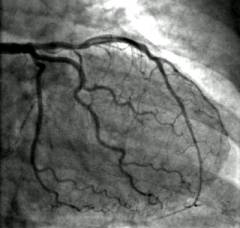

| Поражение коронарных (венечных) артерий, отходящих от аорты и несущих кровь к сердечной мышце. |

|

Хирургическое лечение неспецифического аортоартериита

Обычно выполняется операция шунтирования – врач замещает пораженный участок сосуда на взятый из другой области тела или на искусственный имплантат.